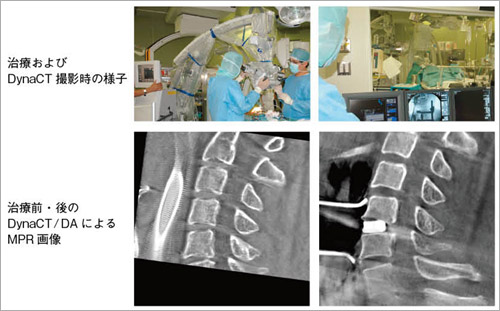

図3 頸椎狭窄患者への外科治療